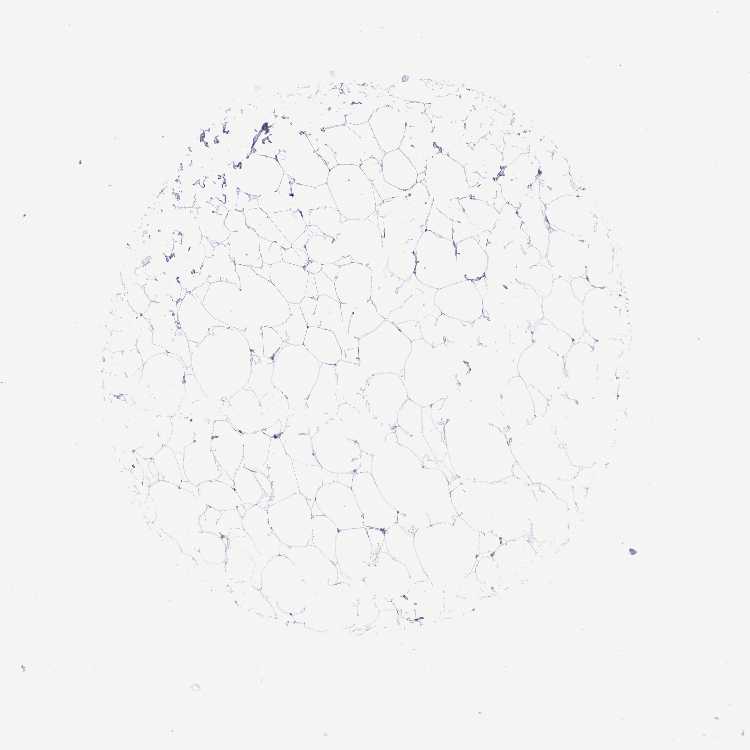

BREAST - Antibody stainingi

Antibody staining in the annotated cell types in the current human tissue is reported as not detected, low, medium, or high, based on conventional immunohistochemistry profiling in selected tissues. This score is based on the combination of the staining intensity and fraction of stained cells.

Each image is clickable and will lead to virtual microscopy that enables deeper exploration of all samples and also displays staining intensity scores, fraction scores and subcellular localization as well as patient and tissue information for each sample.

Antibody HPA063142Antibody CAB024908

Adipocytes Not detectedNot detected

Glandular cells LowLow

Myoepithelial cells LowLow